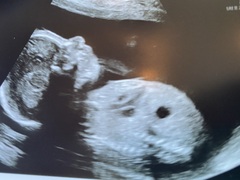

I finally got my 20week re-scan appointment (at 23.5 weeks) but only just!! I rang the hospital yesterday as I hadn’t got a letter or a call, rang at 12 and found out my appointment was for 2pm!! They got to see the last few bits of the heart, but baby made the poor lady (who was training and was specially at the heart part of the training) work for it! Finally got some pics - bubba has a chubby belly ☺️ The blob about the chin is their elbow, they had their had up by their cheek! All is good, we don’t know the sex (we weren’t fussed on finding out to be fair - I know my mindset - not knowing will give me more grit and determination during labour 😂) , but baby also chose to not be in a good position for that as it was! I had to lay on the bed in strange ways just so the could see the one angle of the heart they needed!